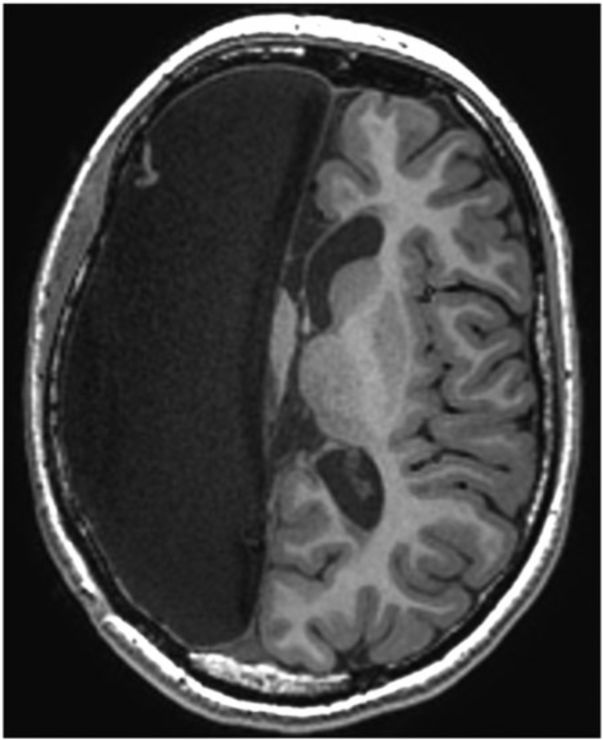

术后随访11年时,已无癫痫发作,能独立行走,左下肢轻度痉挛,足趾活动少,靠膝关节带动足走路;左上臂痉挛性瘫痪,伴同向偏盲。智力正常,正申请高等教育。MRI检查发现,右侧大脑半球缺失。fMRI检查显示,在左侧大脑半球中央前回的左足部运动功能区同右足运动区重叠(图 2),说明健侧半球运动皮质功能重组。

图2. 两侧下肢运动时的fMRI表现。a.右足活动时,显示左侧半球运动皮质内侧部分激活。b.左下肢膝关节运动时,也显示左侧半球运动皮质内侧部分激活,表明左、右两侧半球皮质运动功能区融合重建。

该病案报道支持现有文献报告中提出的病侧运动皮质功能移位至健侧的可能性。但不足之处是,术前没有进行功能性MRI成像以判断是否已经发生健侧半球皮质运动功能的重塑。